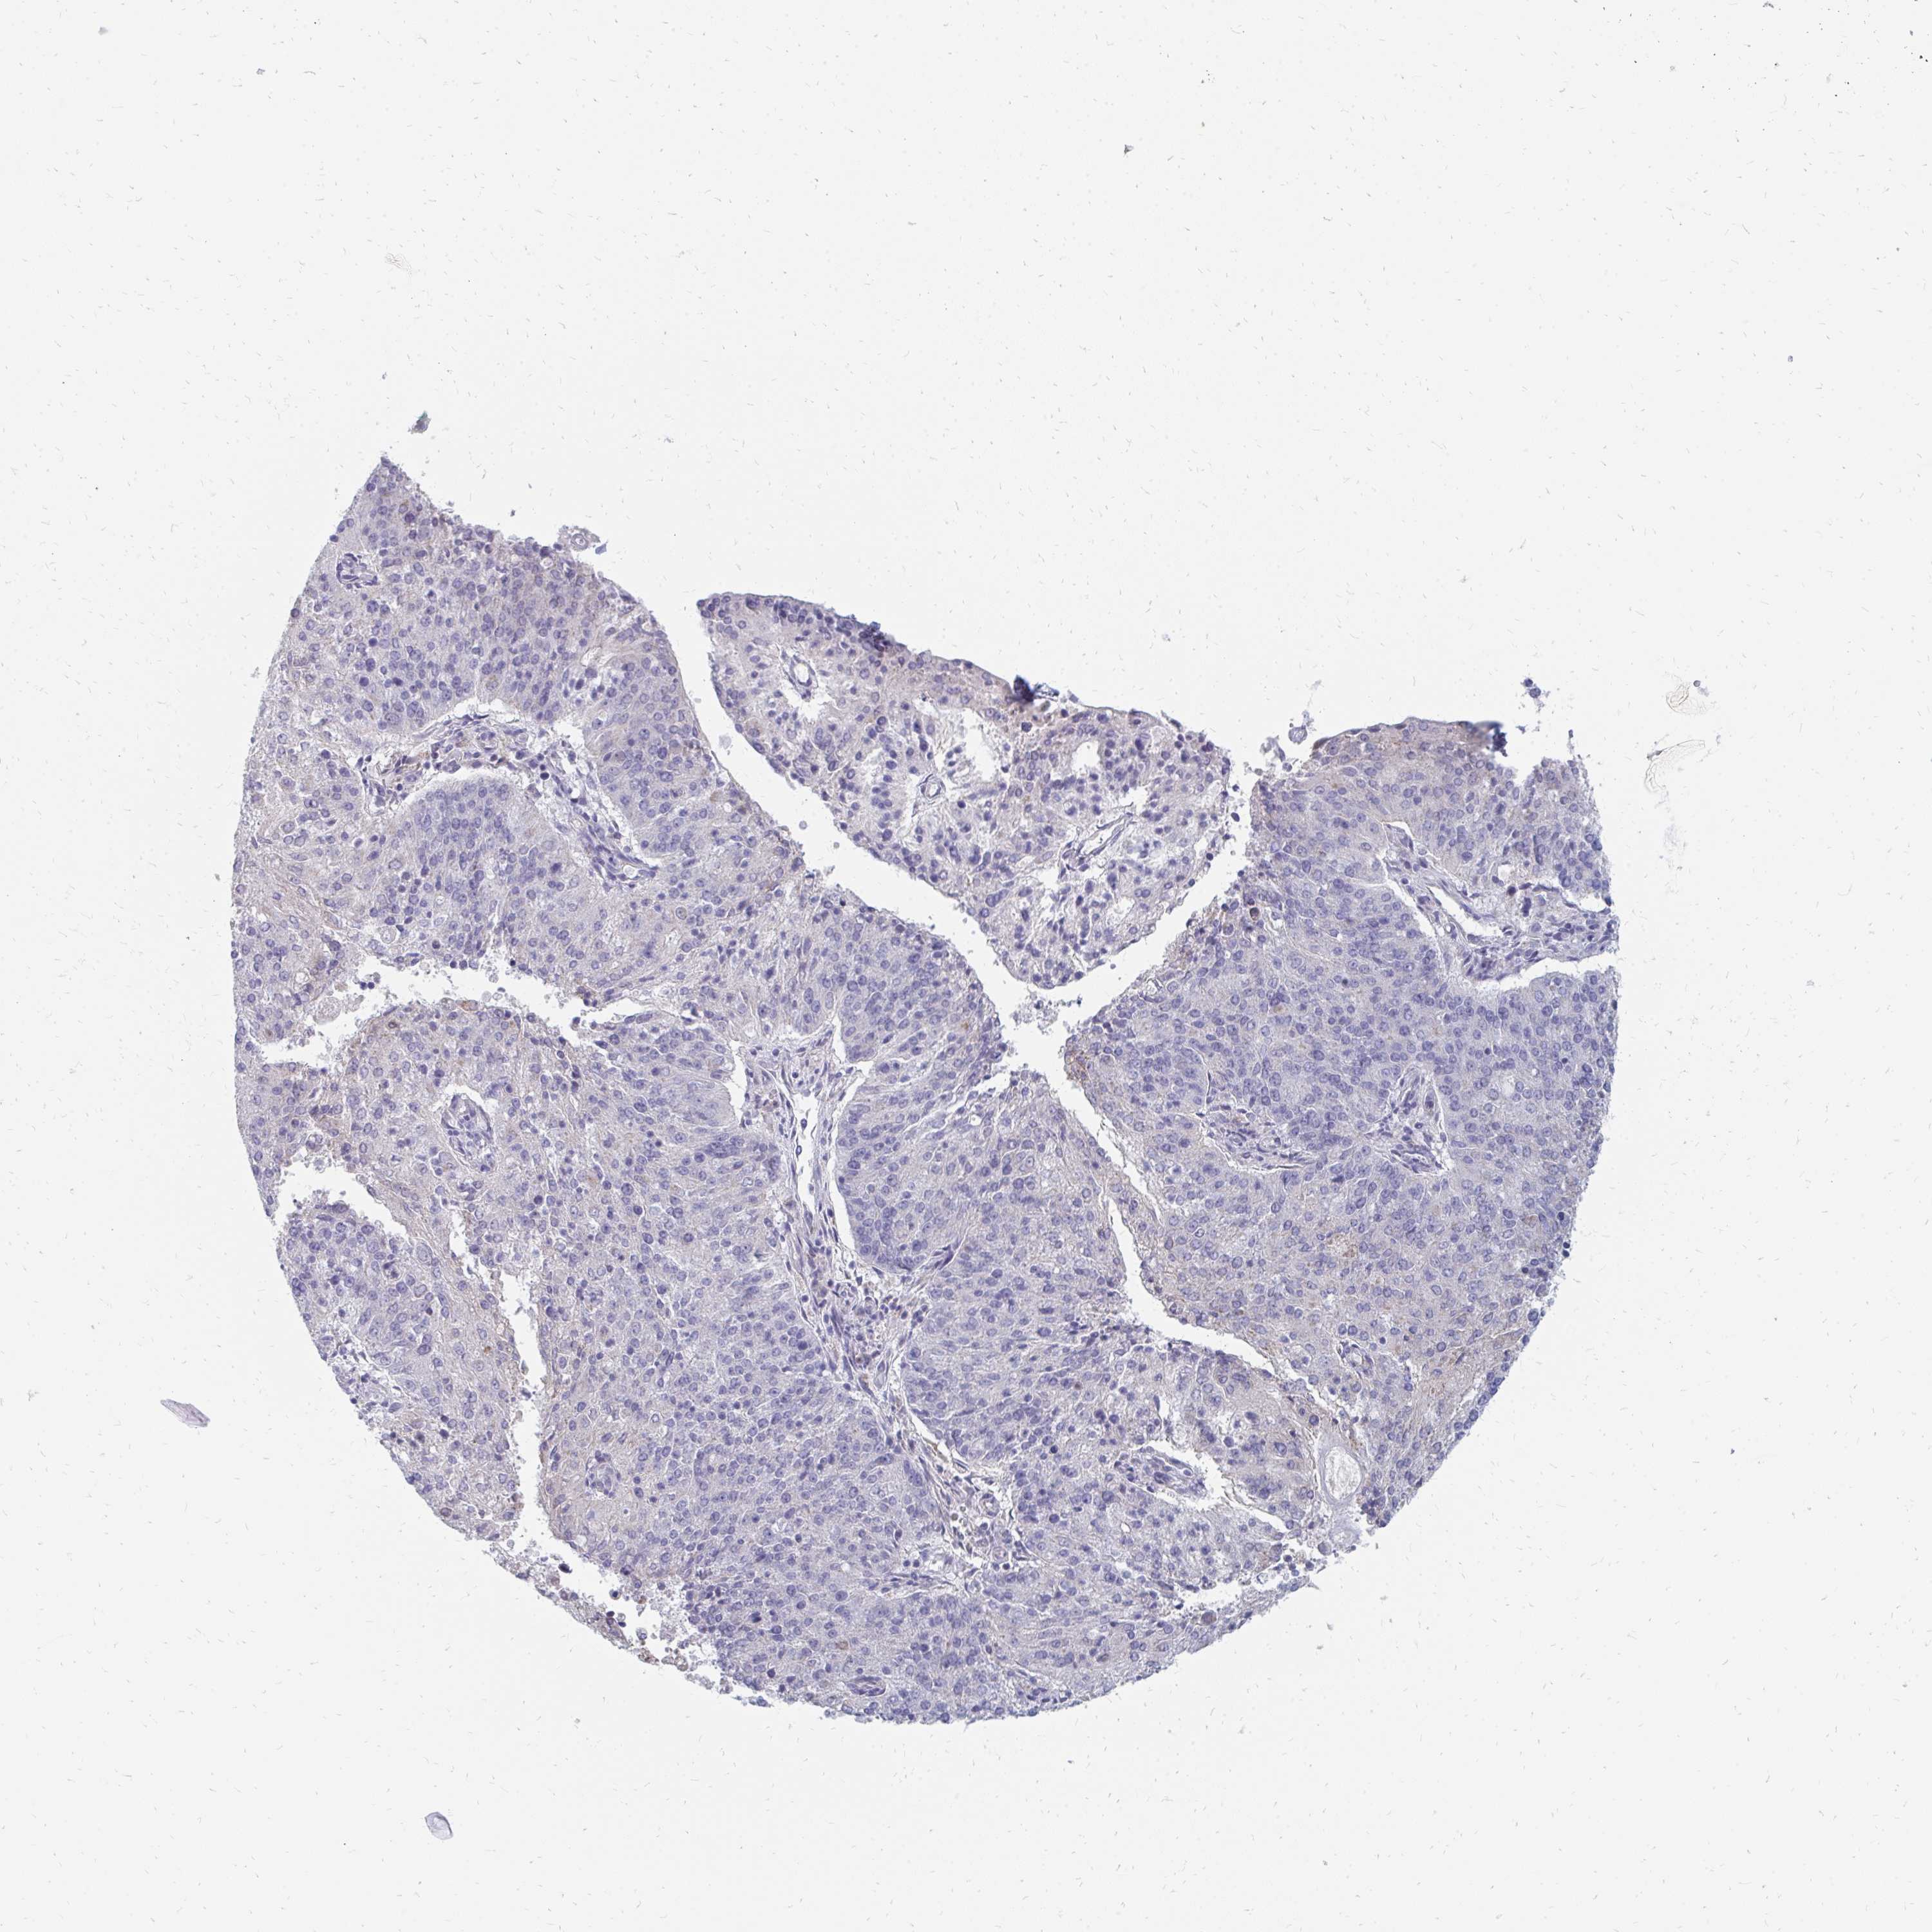

ENDOMETRIAL CANCER - Protein expressioni

A mouse-over function shows sample information and annotation data. Click on an image to view it in a full screen mode. Samples can be filtered based on level of antibody staining by selecting one or several of the following categories: high, medium, low and not detected. The assay and annotation is described here.

Note that samples used for immunohistochemistry by the Human Protein Atlas do not correspond to samples in the TCGA dataset.

Antibody stainingi

Antibody staining in the annotated cell types in the current human tissue is reported as not detected, low, medium, or high, based on conventional immunohistochemistry profiling in selected tissues. This score is based on the combination of the staining intensity and fraction of stained cells.

Each image is clickable and will lead to virtual microscopy that enables deeper exploration of all samples and also displays staining intensity scores, fraction scores and subcellular localization as well as patient and tissue information for each sample.

Antibody HPA060076

Staining

High

Medium

Low

Not detected

Intensity

Strong

Moderate

Weak

Negative

Quantity

>75%

75%-25%

<25%

None

Location

Nuclear

Cytoplasmic/membranous

Cytoplasmic/membranous,nuclear

Adenocarcinoma, NOS